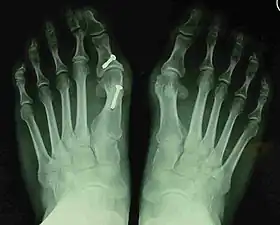

- For recurrence correction after osteotomy procedure (Fig. 8)

Late deformity recurrence can happen after osteotomy (bone-breaking) procedures because osteotomy surgeries do not specifically stabilize first metatarsal bone.